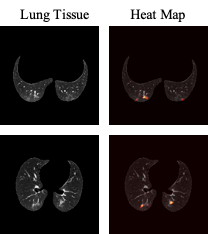

In addition to the aforementioned numerical results, we incorporated the GRAD-CAM localization mapping method to visualize the distinctive patterns in a chest CT scan recognized by the last convolutional layer of the CT-CAPS. Fig. 4 illustrates the recognized abnormal regions for two lung samples containing small evidences of COVID-19 infection. In these two examples, we can observe that the model correctly identified the regions of infection, which had the highest contribution to final decision.

Refer to caption

Fig. 4: The heat-maps created by the GRAD-CAM approach from the last convolutional layer of the CT-CAPS framework for two sample images with COVID-19-related evidences of infection.